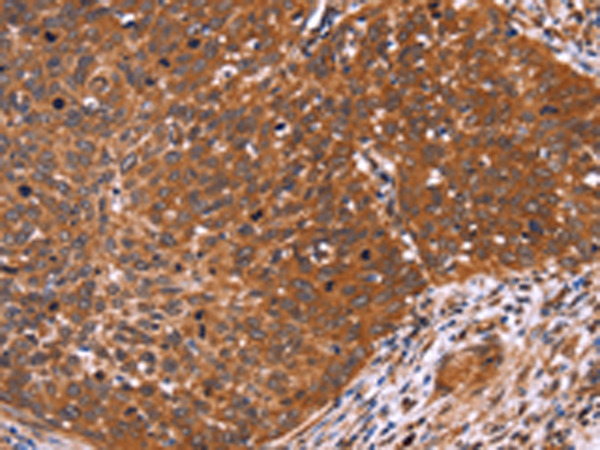

IHC positive control: |

Human cervical cancer and human colon cancer |

IHC Recommend dilution: |

100-300 |